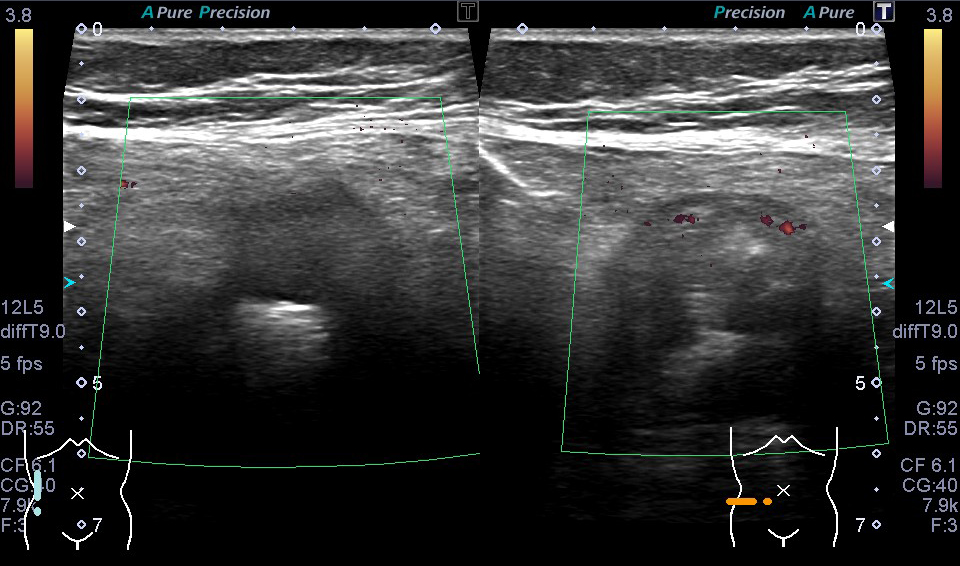

超音波(エコー) 診断画像

- 粉瘤

- 膝窩靭帯炎

- 乳腺症

- 乳がん

- 静脈瘤